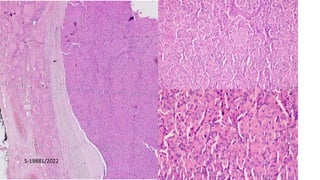

Follicular thyroid adenoma with papillary architecture

27/M

, 27/M with thyrotoxicosis

Papillary lesions: D/D

Sandersons Polsters

S-19881/2022

Histology Pictures

Essential diagnostic criteria

Essential:

Non-invasive, encapsulated, follicular-

patterned tumour.

Lack of nuclear features of papillary

thyroid carcinoma.

Architecture and cytomorphology of FA

should be distinct from the background

thyroid parenchyma.

Mitoses are usually rare (<3 mitoses per 2 mm2), and coagulative tumour necrosis is absent